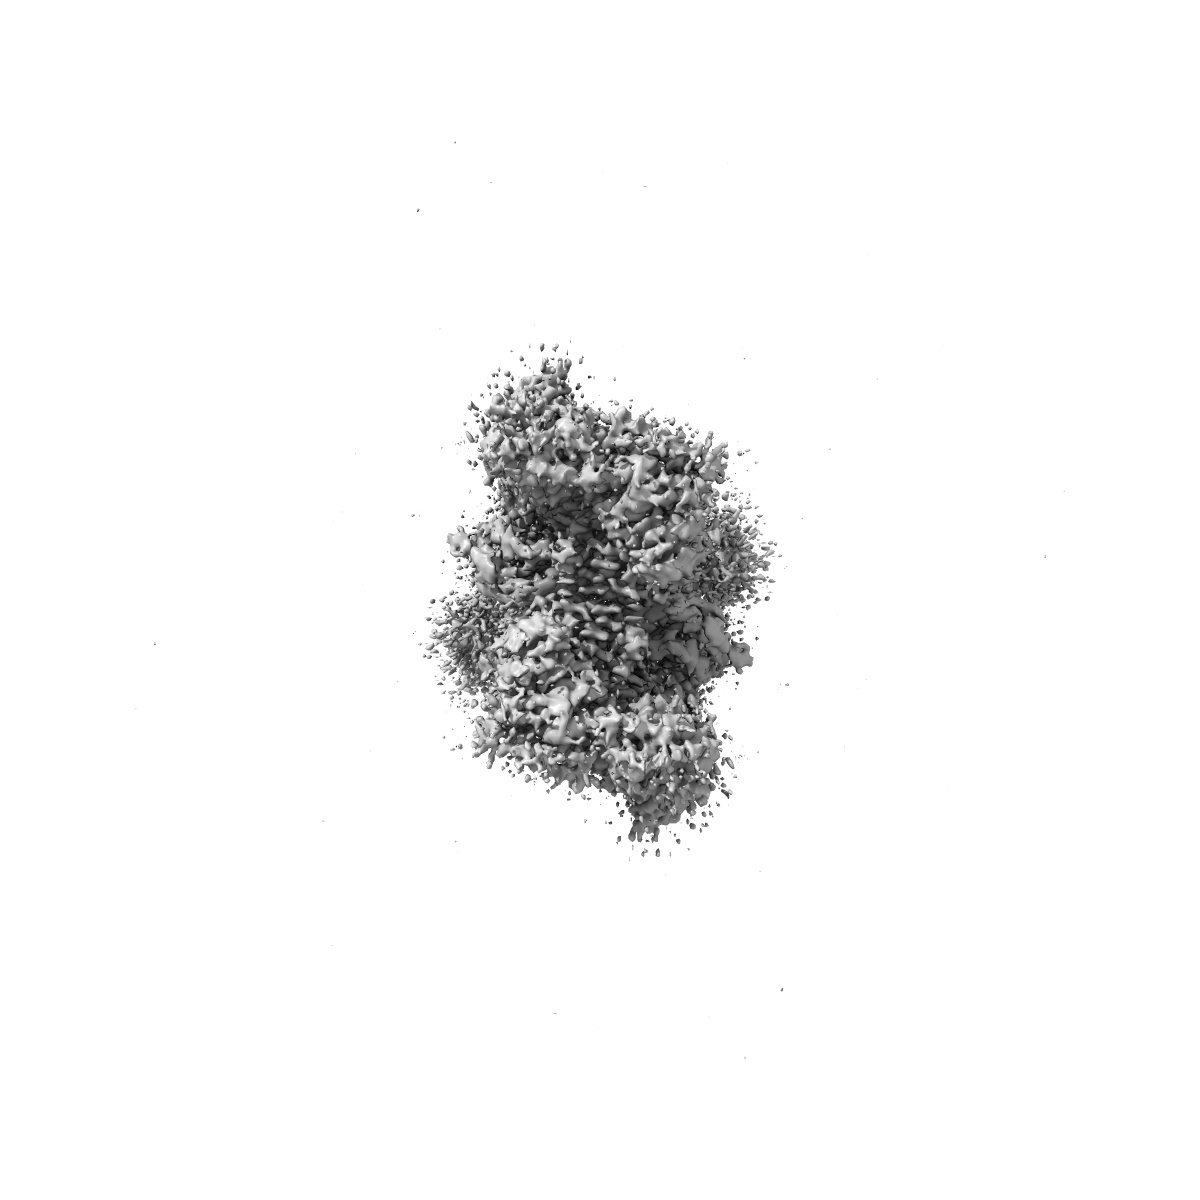

Structure of AMPA receptor GluA2 complex with auxiliary subunits TARP gamma-5 and cornichon-2 bound to competitive antagonist ZK, channel blocker spermidine and antiepileptic drug perampanel (closed state)

Single-particle3.01 Å

Sample: GluA2-TARP gamma5-cornichon-2

Modulation of GluA2-gamma 5 synaptic complex desensitization, polyamine block and antiepileptic perampanel inhibition by auxiliary subunit cornichon-2.

(2023) Nat Struct Mol Biol , 30 , 1481 - 1494